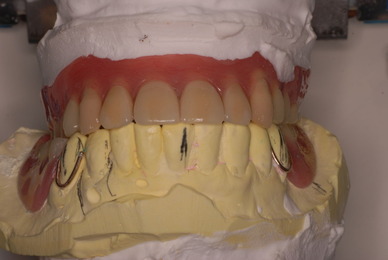

上の総義歯はまっったくはずれませんでした。下顎の入れ歯では若干痛みが出そうなので噛み合わせの調整をしています。口腔内では時間がかかりすぎるので器械に付けて調整しています。

下顎が右にシフトしているので噛み合わせはとても慎重にしました。下の方が頬側にないと安定せず噛めないのです。

左側の噛み合わせはまともにできます。